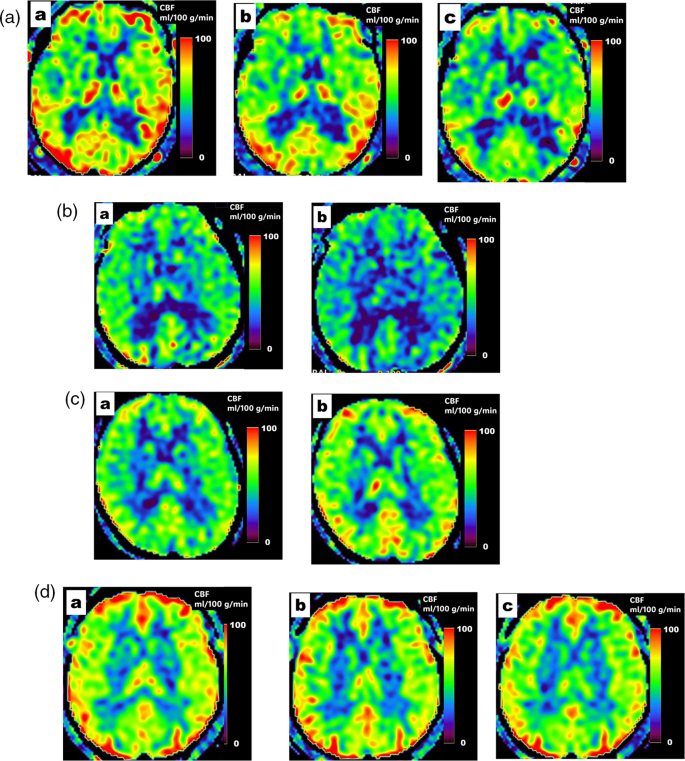

The number of cases in each subgroup was 27 in Group CHP and CBF-, 19 in Group NoCHP and CBF-, 18 in Group NoCHP and CBF+, and 9 in Group ConstantCBF (6 patients had CHP before anti-CGRP therapy). Typical imaging findings for each group are shown in Fig. 2A–D.

Example patients from the four groups defined by changes in CBF after anti-CGRP therapy. (A) Representative patient from Group CHP and CBF-: A 75-year-old woman with episodic migraine (MHD: 10, HIT-6: 66) without insomnia presented with CHP on ASL before treatment (a). After administration of galcanezumab, no changes are observed on ASL images (b). After switching to erenumab, CHP has disappeared and treatment is considered to have been 100% efficacious (MHD: 0, HIT-6: 36) (c). Please see Supplementary Figure 1 for a depiction of the ROIs in the cortical region. (B) Representative patient from Group NoCHP and CBF-: A 64-year-old man with chronic migraine (MHD: 30, HIT-6: 78), insomnia, morning migraine, WMHs on MRI, and no CHP on ASL (a). After administration of erenumab, the patient achieves a 50% reduction in MHDs (MHD: 8, HIT-6: 50), but insomnia and morning migraine do not improve, and CBF is lower than normal in all ROIs (b). Please see Supplementary Figure 1 for a depiction of the ROIs in the cortical region. (C) Representative patient from Group NoCHP and CBF+: A 44-year-old woman with episodic migraine (MHD: 10, HIT-6: 60), insomnia and morning migraine but no CHP on ASL (a). After administration of galcanezumab, insomnia and morning migraine improve, CBF increases, and 100% treatment efficacy is achieved (MHD: 0, HIT-6: 36) (b). Please see Supplementary Figure 1 for a depiction of ROIs in the cortical region. (D) Representative patient from Group ConstantCBF: A 40-year-old woman with episodic migraine (MHD: 5, HIT-6: 60) and CHP on ASL despite insomnia (a). Neither galcanezumab (b) nor erenumab administration (c) produce changes on ASL, and no therapeutic response is achieved (MHD: 5, HIT-6: 56). Please see Supplementary Figure 1 for a depiction of ROIs in the cortical region.